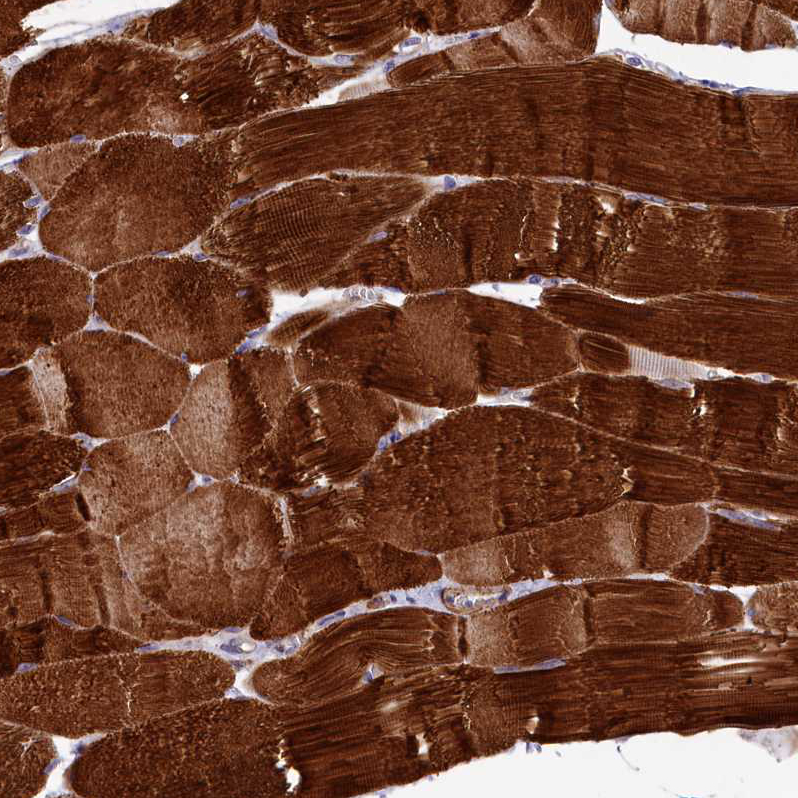

Immunohistochemical staining of human skeletal muscle shows strong cytoplasmic positivity in myocytes.